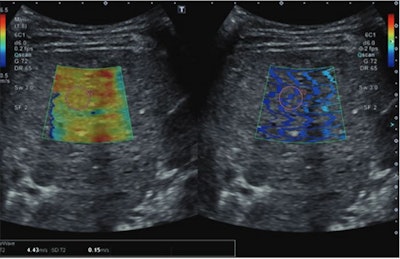

Ultrasonic images show a 15-year-old patient with prior Fontan circulation and high initial liver stiffness (4.43 m/s). The patient subsequently developed Fontan circulatory failure during follow-up at age 19 and underwent heart transplantation. The left image is a color elastogram (scale to left), and the right image is wave propagation image, reflecting quality of shear-wave acquisition. The pink circle indicates the sample region of interest. Image courtesy of the ARRS.The researchers found that the median initial liver stiffness was 2.22 m/s, the median initial VAST score was 0, and the median follow-up VAST score was 1 (p = 0.04). Also, Fontan circulatory failure occurred in 37 patients (31%), with a median follow-up of 3.4 years.